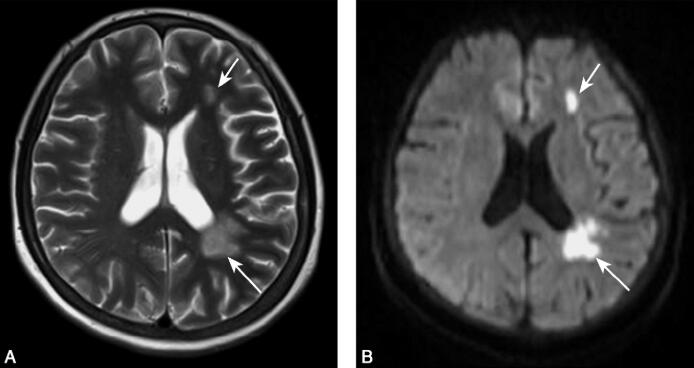

辅助检查:颅脑MRI(2010年11月17日):左侧额颞顶枕、脑干多发性缺血梗死灶。MRA:双侧颈内动脉未显示,后交通动脉代偿双侧大脑前动脉和大脑中动脉,大脑前动脉和大脑中动脉纤细;右侧大脑后动脉较对侧粗(图1、图2)。

图1 颅脑MRI(2010年11月17日):A.轴位MRI T2加权像显示左侧额颞、顶枕交界区散在片状长T2信号(箭头);B.轴位DWI显示上述病灶高信号影(箭头)